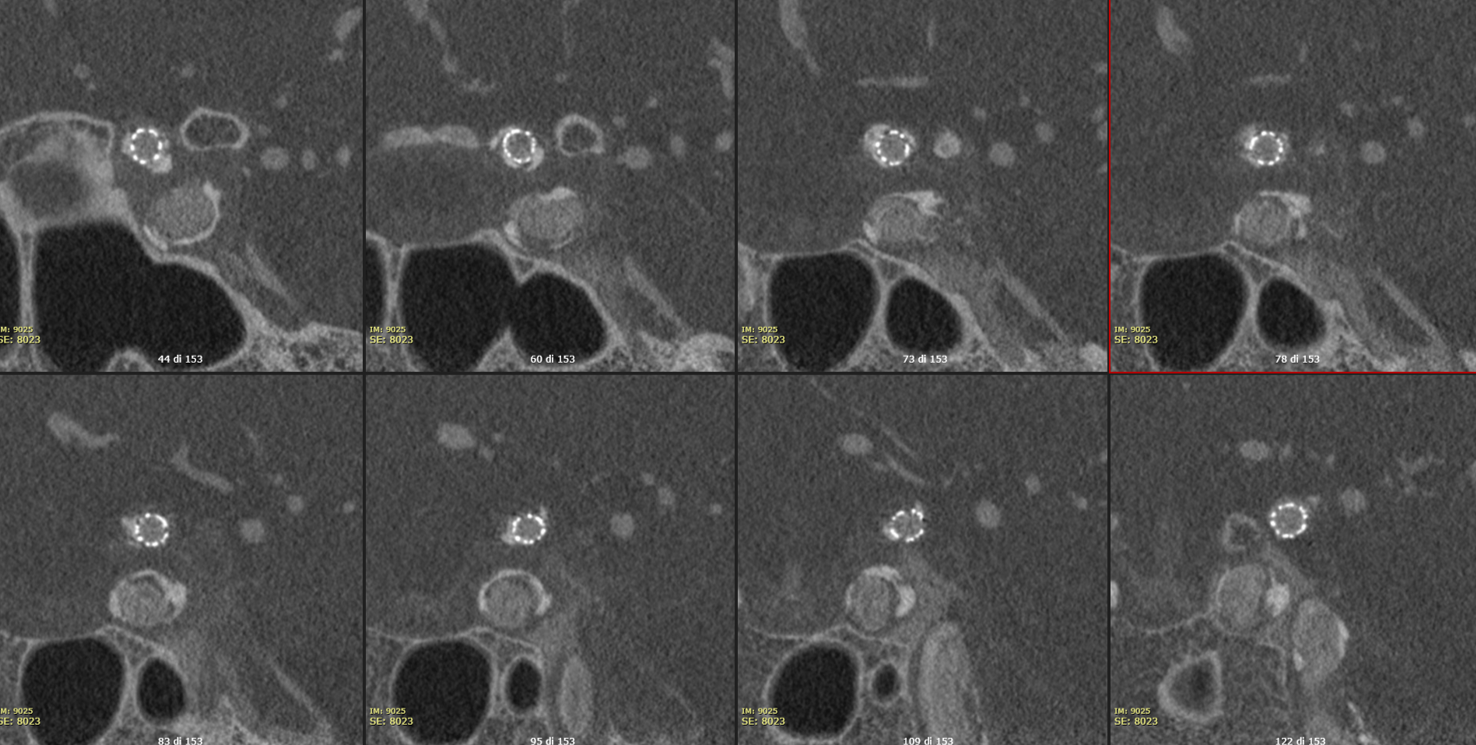

The Vaso-CT (22 cm FOV, 20 seconds acquisition, pure contrast – 300 mg/ml -manual injection 20 ml with a 20 ml syringe) shows the highly irregular atherosclerotic plaque with small residual lumen